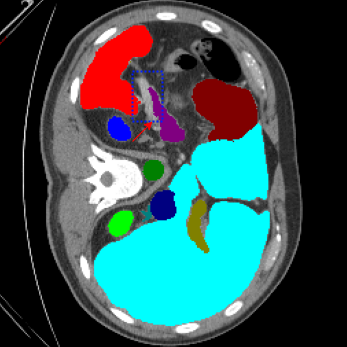

We begin by qualitatively inspecting our model. Figure 3 compares the output of LoGoNet to the best performing baseline model in BTCV dataset, i.e., DiNTS Search (more qualitative comparisons can be found in appendix section 11). We see that our model particularly excels in segmenting organ boundaries. This can be attributed to our effective strategy for extracting local-range dependencies, which plays a crucial role in extracting details from input data. Our model’s adeptness in capturing long-range dependencies allows it to grasp contextual information that extends over significant distances within the data. Simultaneously, its proficiency in handling short-range dependencies ensures precision in capturing localized patterns.